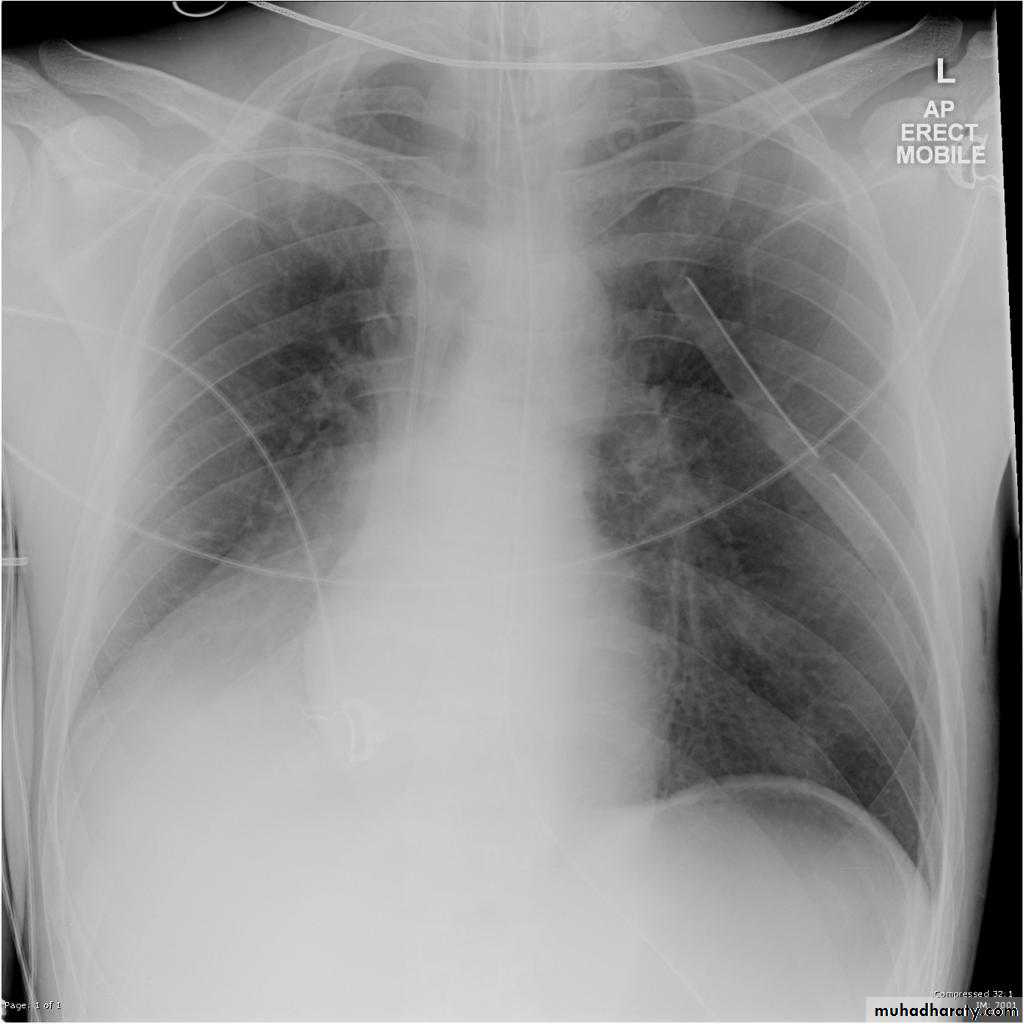

Pleural effusionPleural effusion tends to be used as a catch-all term denoting a collection of fluid within the pleural space. This can be further divided into exudates and transudates depending on the biochemical analysis of aspirated pleural fluid. Essentially it represents any pathological process which overwhelms the pleura's ability to reabsorb fluid.

Radiographic appearances

Plain radiographChest radiographs are the most commonly used examination to assess for presence of a pleural effusion, however it should be noted that on a routine erect chest x-ray as much as 250-600 ml of fluid is required before it becomes evident 6. A lateral decubitus film is most sensitive, able to identify even a small amount of fluid. At the other extreme, supine films can mask large quantities of fluid.

CXR (erect)

Both PA and AP erect films are insensitive to small amounts of fluid. Features include:

blunting of the costophrenic angle

blunting of the cardiophrenic angle

fluid within the horizontal or oblique fissures

eventually a meniscus will be seen, on frontal films seen laterally and gently sloping medially (note:

A subpulmonic effusion (infrapulmonary effusion) may be seen when there is previously established pulmonary disease, but can also be encountered in normal lungs , They are more common on the right, and usually unilateral

with large volume effusions, mediastinal shift occurs away from the effusion (note: if coexistent collapse dominates then mediastinal shift may occur towards the effusion)